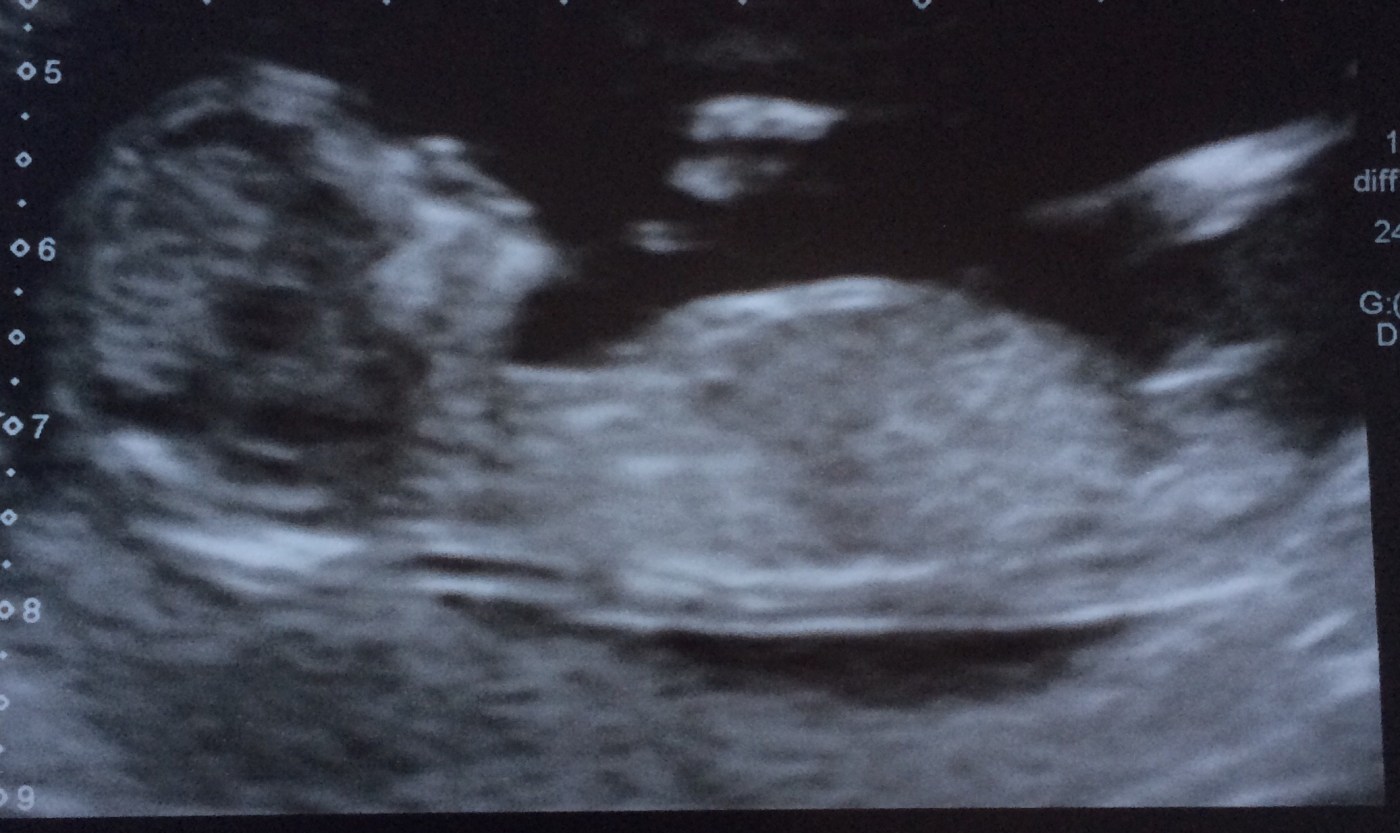

Still, once you take a positive test there’s a timeline to follow. The post stick-pee step (again according to the NHS website, now my bible) was to make an appointment with a GP or midwife. I phoned and spoke to a nice lady who told me my estimated due date (September 28, later updated to September 24) and booked me in to see the midwife (on 21 February) and for a growth scan (19 March).